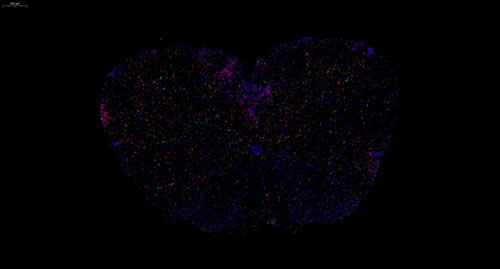

小鼠脊髓 普通切片扫描(荧光双标 三色)